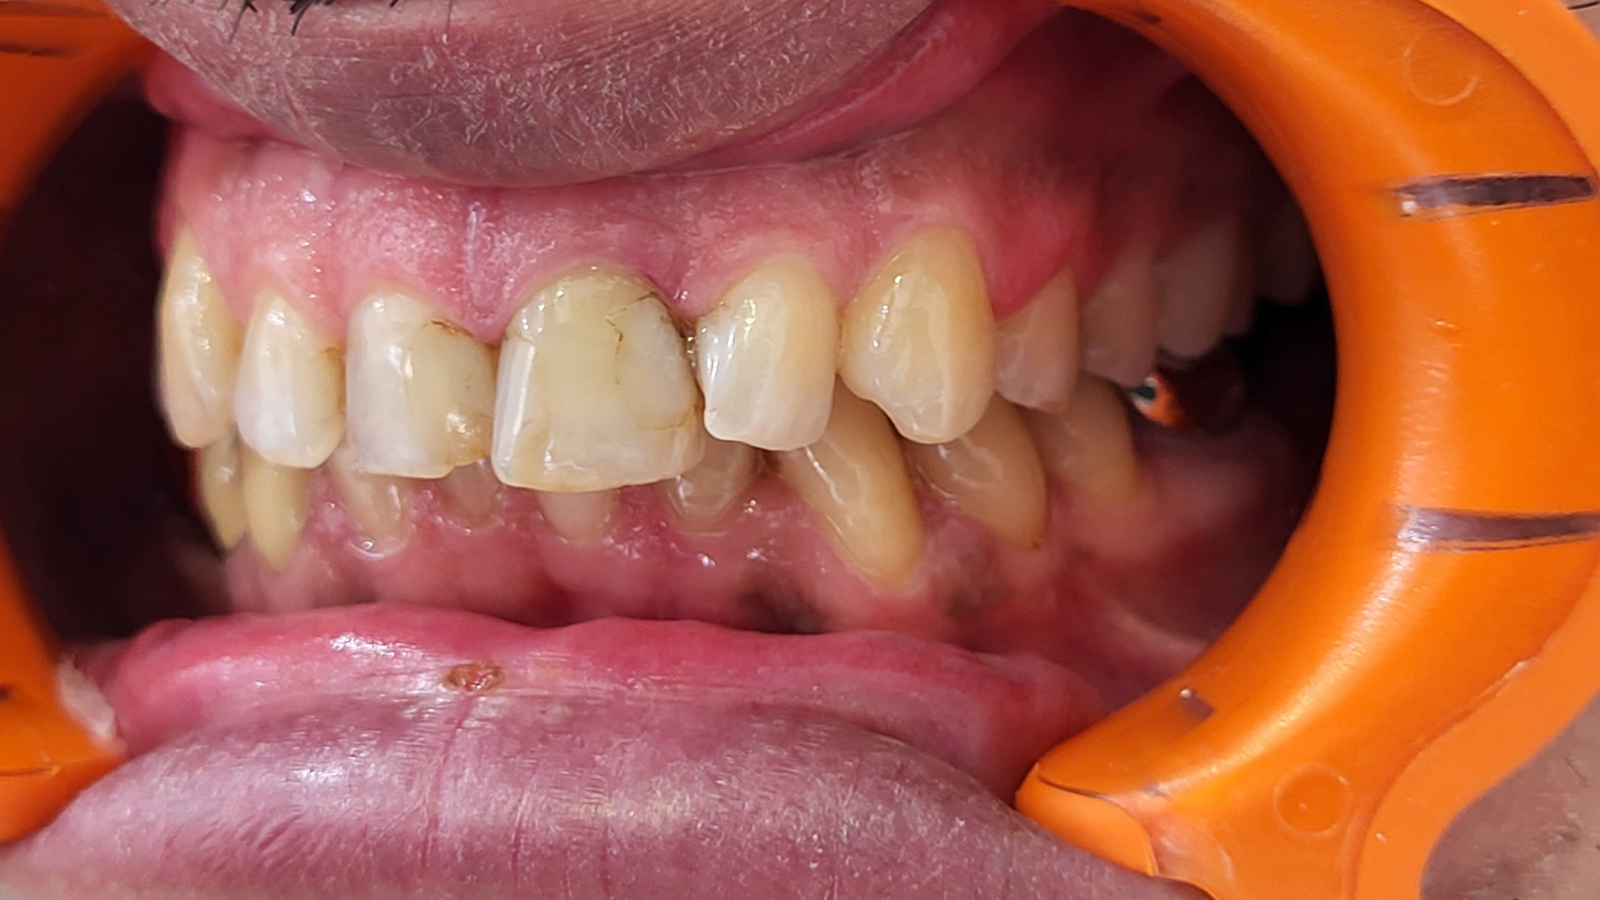

Réhabilitation complète avec mise en charge immédiate (4 implants bas / 6 implants haut)

Le patient se présente avec des dents qui bougent, en haut et en bas.

Nous avons commencé par la mâchoire inférieure avec 4 implants et une mise en charge immédiate.

Trois mois après, le haut a été fait avec le même principe avec 6 implants.

Cette fois-ci, il existait un déficit osseux, résolu par une technique d’expansion sans avoir recours à la greffe d’os.

Les prothèses réalisées sont vissées, ce qui permet de les enlever, les nettoyer une fois par an, ou résoudre n’importe quel problème.